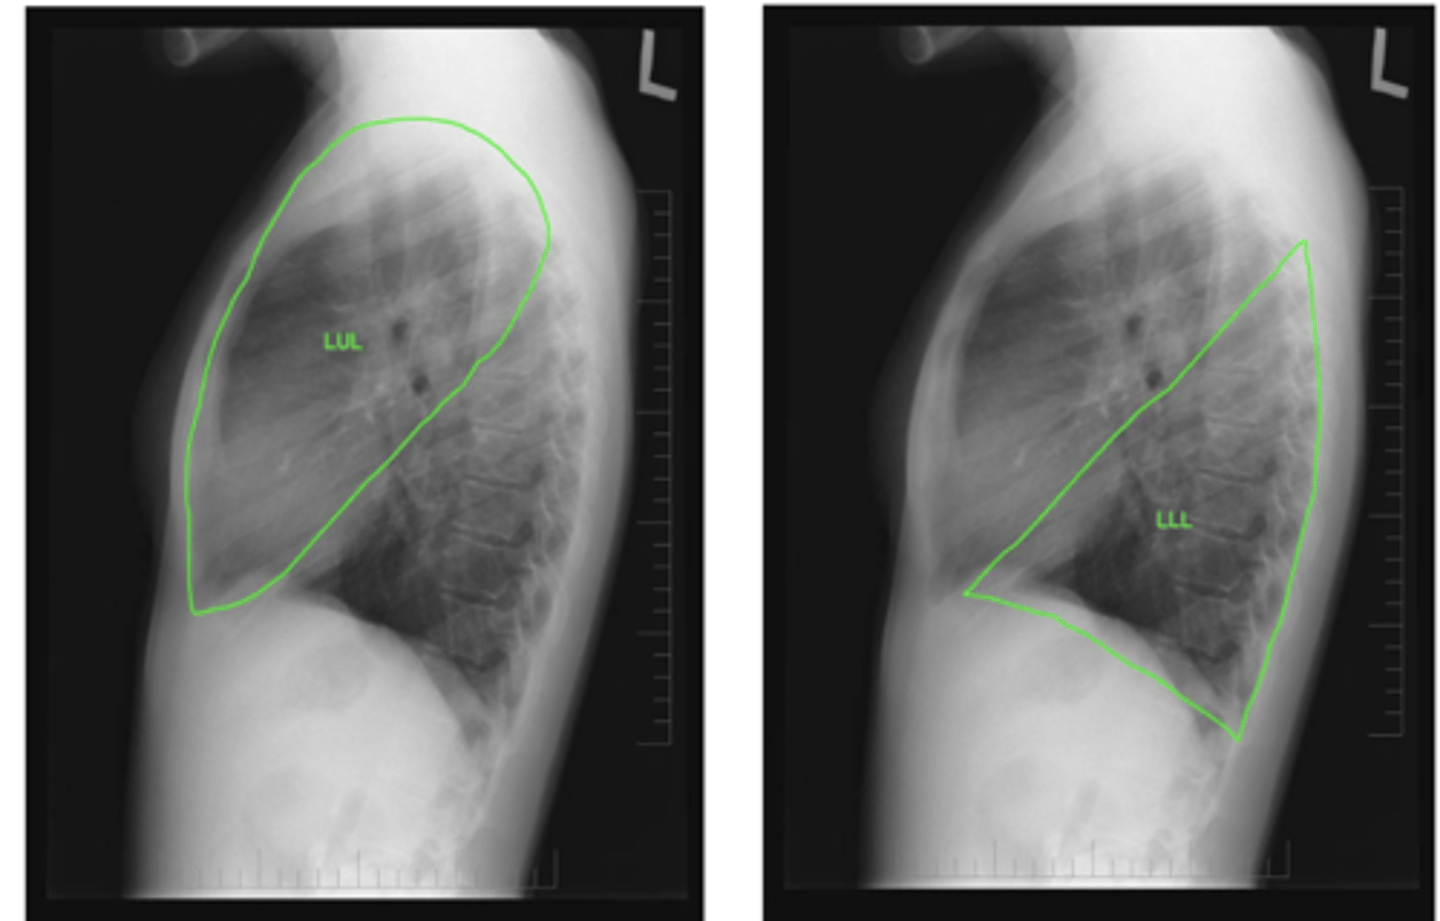

ID lobes of lungs on back of card (lateral right)

refer to picture

<p>refer to picture</p>

ID lobes of lungs on back of card (lateral left)

refer to pic

<p>refer to pic</p>